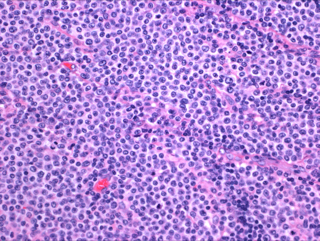

肿瘤细胞广泛侵润,具有明显亲上皮性,包括隐窝和表面肠上皮。肠绒毛变形、扩大。细胞中等大小,形态单一,核圆,染色质精细分散,无明显核仁,胞浆较淡相对较多。无混合炎性细胞,坏死也较 EATL 少。

免疫表型:绝大多数病例 CD3+、CD8+、CD56+、MATK+、TCR-γδ+(少数 TCR-β+),罕见 TCRgamma+/TCRbeta+,TIA1 也常阳性(但粒酶 B 和穿孔素常阴性)。CD5 阴性,EBV 阴性(可有散在 B 细胞阳性)。